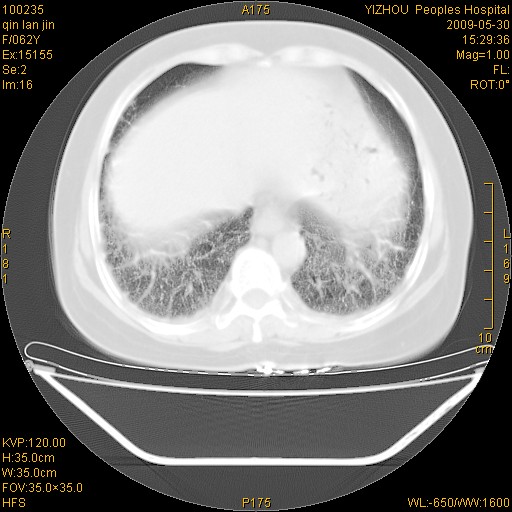

标题: CT20268:肺泡癌?间质性肺炎? [打印本页]

标题: CT20268:肺泡癌?间质性肺炎?

女,62岁,近二年经常咳嗽,近二个月,消瘦、乏力。

前面一张胸片是今天照的,后面一张胸片是去年9月份的。

弥漫性双肺间质纤维化。

两肺弥漫性间质性病变(间质性肺炎伴肺间质纤维化?)。

弥漫性双肺间质纤维化

间质性肺炎伴肺间质纤维化。